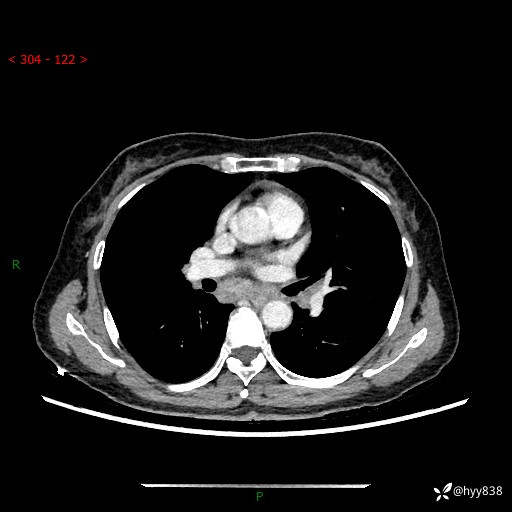

【患者信息】:58岁/女

【主诉】:体检发现肺结节

【检查】:胸部CT平扫+增强

结节病 (44)

小细胞癌 (19)